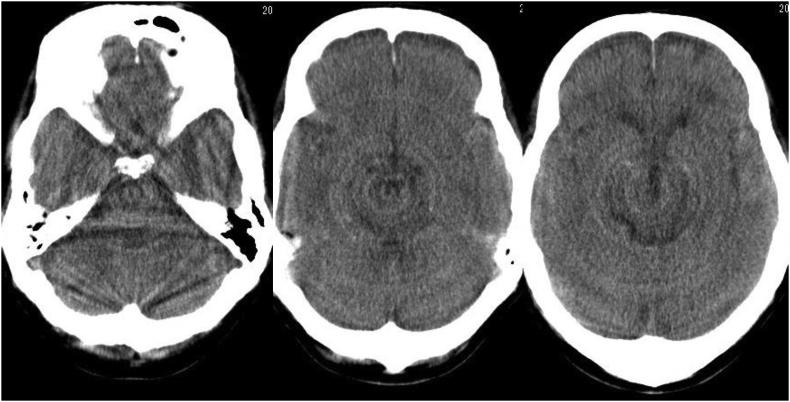

Cortical deafness is a rare condition and is usually caused by bilateral cerebral lesions. Several cases of sudden cortical deafness caused by ischemic stroke or hypertensive intracerebral hematoma have been reported, however, no cases of traumatic cortical deafness were identified in our literature search. We experienced a case of delayed traumatic intracerebral hematoma (DTICH) presenting as cortical deafness. In our patient, warfarin intake seemed to be a risk factor for DTICH. Head injury may adversely affect the coagulability and thrombolysis. A high risk of DTICH after traumatic head injury should be kept in mind when encountering patients taking anticoagulants.

皮质聋是一种罕见的病症,通常由双侧脑部病变引起。已有数例由缺血性中风或高血压性脑出血导致的突发性皮质聋的病例报道,然而,在我们的文献检索中未发现外伤性皮质聋的病例。我们遇到了一例以皮质聋为表现的迟发性外伤性脑内血肿(DTICH)。在我们的患者中,服用华法林似乎是DTICH的一个危险因素。头部损伤可能会对凝血和溶栓产生不利影响。遇到服用抗凝剂的患者时,应牢记外伤性脑损伤后发生DTICH的高风险。